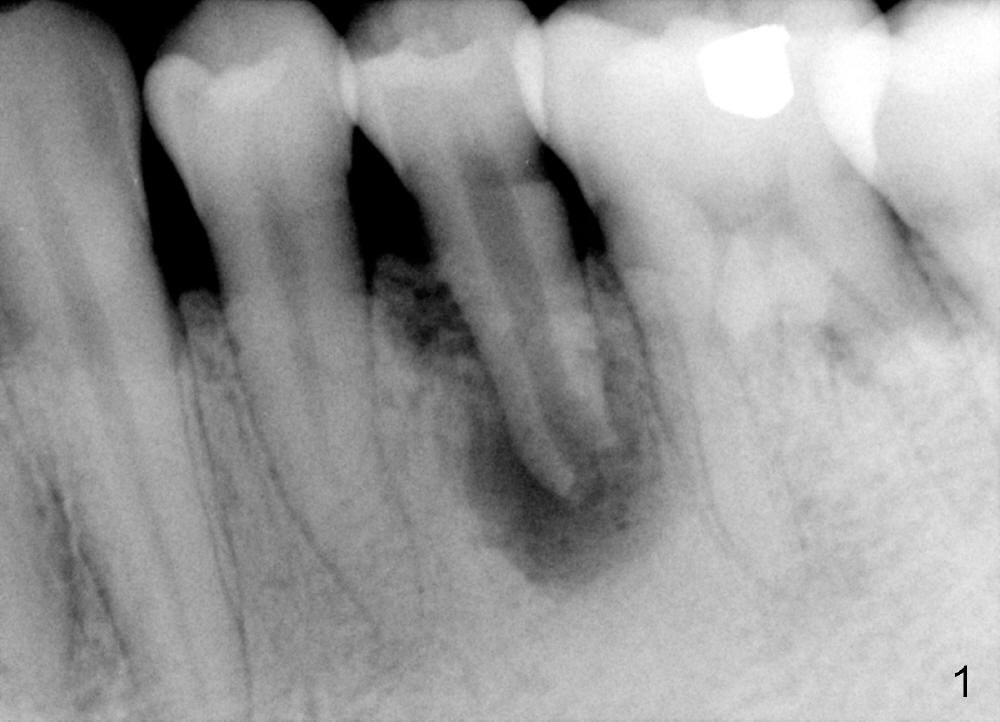

A 40-year-old Chinese man has periodic (once a month) mild pain and swelling in the lower left quadrant. Clinical exam reveals dens evaginatus (Fgi.1': <) in #20. Upon pressure from mouth mirror handle, there is limited amount of purulent discharge from the fistula (Fig.1": <). Preop PA shows a large canal with large periapical radiolucency (Fig.1). RCT started on Aug 6, 2010 with #70 file at 20 mm (Fig.2), #120 file at 16 mm (Fig.3) and CaOH paste in the canal (Fig.4). The dressing changed on Oct 8, 2010 (Fig.5). RCT finished on Jan 25, 2011 with master cone (rolled with several gutta perchae) (Fig.6), lateral condensation (Fig.7) and after vertical condensation and build-up (Fig.8). The canal was wet in the last two appointments with no sign of apexification. Follow up is done in 7 months (Fig.9), 11 months (Fig.10) and 18 months. Although the patient reports no pain after the treatment, the fistula remains with purulent discharge. The patient does not accept apical surgery. What should we do? Retreat with MTA (1,2,3)?